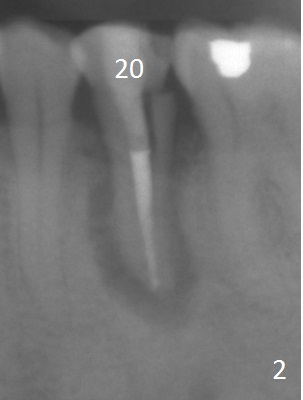

A 53-year-old man (probably bruxer, long roots) has 3 missing teeth (Fig.1 #14,18,29) and 1 fractured tooth (Fig.2 #20).  The fractue is associated with deep buccal pockets.  The buccal plate is most likely defective.  After extraction (Metronidazole), start osteotomy lingual and mesial (Fig.3 red long arrow) to reduce damage to the Mental Loop (Fig.4 red dashed line).  Damage to the Incisive Canal (yellow dashed line, the continuum of the Inferior Alveolar Canal after giving off the Mental Loop) is less significant.  Since the defect is long, use the longest implant and place it deep.  A long abutment (7 mm, green) with 5 mm cuff (pink) is required.  To have sufficient buccal gap for bone graft and probably membrane, the smallest two-piece implant is necessary (3.8 mm).